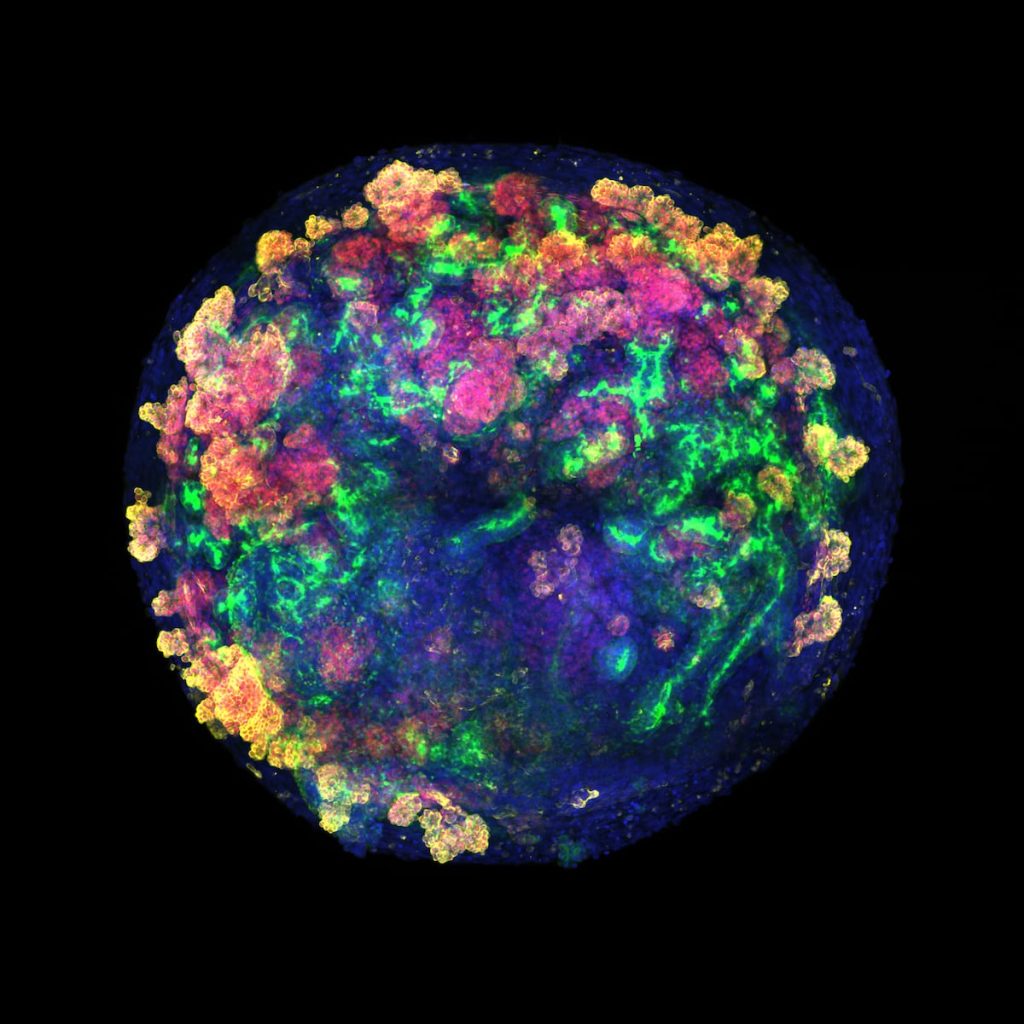

A pesar de que España es referencia mundial en trasplantes, cada año miles de personas se quedan sin recibir el riñón donado que necesitan. Lo mismo sucede con otros órganos. Y a nivel global el problema es muchísimo más grave, con millones de afectados y unas listas de espera que no dejan de crecer por el envejecimiento de la población. En Estados Unidos, diecisiete personas mueren cada día esperando un riñón trasplantado, y cada nueve minutos se suma un paciente más a la lista de espera. La situación amenaza con colapsar los sistemas de salud dentro de unos años. Hoy, un avance biomédico liderado por investigadores españoles abre una nueva vía para aliviar las listas de espera de trasplantes usando minirriñones humanos.Estos organoides empiezan siendo un amasijo de unas pocas células madre, y después crecen hasta ser unas pelotitas algo más pequeñas que la cabeza de un alfiler. En ese momento ya tienen un armazón de células especializadas que se asemeja al de los diferentes órganos del cuerpo, una característica que los hace ideales para estudiar enfermedades o hacer pruebas de toxicología.Más informaciónEl nuevo trabajo da un salto para explorar si estas estructuras también pueden usarse para trasplantes en humanos. Los investigadores han desarrollado organoides de riñón a partir de células madre humanas, los han cultivado y, por primera vez, han demostrado cómo producirlos en gran cantidad y de forma rentable, lo que acerca su futura aplicación a pacientes.El trabajo lo ha dirigido la bióloga barcelonesa de 47 años Nuria Montserrat, profesora de investigación ICREA en el Instituto de Bioingeniería de Cataluña (IBEC) hasta hace poco más de un año, y actual consejera de Investigación y Universidades de la Generalitat de Cataluña. Antes de asumir su cargo en el Gobierno de Salvador Illa, Montserrat llevaba más de una década impulsando el uso de estos cultivos celulares en medicina regenerativa. Ahora, junto a científicos de varias entidades españolas, incluida la Organización Nacional de Trasplantes, e investigadores de la Universidad de California, su equipo ha conseguido injertar por primera vez organoides renales humanos en riñones porcinos gracias a máquinas de perfusión normotérmica, utilizadas habitualmente en el quirófano para mantener el órgano vivo y oxigenado fuera del cuerpo antes de un trasplante. Esta maniobra permite la integración de las células humanas en el órgano del animal. Por primera vez, los investigadores han vuelto a trasplantar estos riñones a los animales vivos a los que se los habían extirpado, y han demostrado su funcionalidad y ausencia de rechazo. El estudio se ha publicado este viernes en la revista especializada Nature Biomedical Engineering.El paso siguiente, explica Montserrat a EL PAÍS, es ensayar la técnica con vísceras de cadáveres humanos. “Cada año se descartan más de 1.000 riñones que no son aptos para entrar en el proceso de trasplante. Ahora tenemos la oportunidad de usarlos para investigación”. El objetivo final es reducir las listas de espera de trasplantes y aumentar el número de riñones disponibles para su injerto.Fabricar organoides humanos que valgan para estos usos es complejísimo. “Hace 10 años”, detalla Montserrat, “nuestra idea era hacer un riñón humano entero, desde cero, pero es algo muy naíf”. “El riñón es uno de nuestros órganos más complejos, con 23 tipos de células especializadas diferentes”, añade. Dos médicos realizan el trasplante de riñón con organoides humanos en un cerdo vivo.IBECLos nuevos organoides renales son apenas visibles en el momento de integrarse en los órganos de cerdo —deben medir unas 200 micras para poder entrar por las arterias sin obstruirlas— pero ya tienen 19 tipos distintos de células específicas. Gracias a la colaboración con instituciones repartidas por España, que son el armazón de una futura red (desarrollo de miniórganos en Barcelona, experimentos y trasplantes al cerdo en A Coruña usando máquinas de perfusión fabricadas en Zaragoza, y análisis de la respuesta inmune en el Instituto de Salud Carlos III de Madrid), se ha demostrado esta técnica “como prueba de concepto”.La escasez global de órganos ha impulsado el uso de vísceras de cerdo para trasplantes en humanos. Hasta ahora, uno de los casos más exitosos había sido el de Tim Andrews, un estadounidense de 67 años al que se le injertó un riñón porcino que previamente había sido modificado genéticamente para eliminar virus y hacerlo más compatible con su organismo. La operación fue un éxito hasta hace apenas unos días, cuando los médicos del Hospital General de Massachusetts se lo extirparon porque estaba dando problemas. Andrews vivió 271 días con el implante, un récord mundial. Los dos primeros pacientes que recibieron estos trasplantes murieron poco después de la intervención, y el tercero pudo llevarlo durante 130 días hasta que su organismo lo rechazó. Otros pacientes vivos también han recibido trasplantes experimentales de corazón e hígado de estos animales, aunque su efectividad aún es muy incierta. Por ahora, este tipo de intervenciones se ven como un puente con el que ganar tiempo hasta que llega en órgano humano necesario.Los organoides humanos se suman ahora como una nueva vía, opina Jordi Ochando, inmunólogo del Carlos III y del Hospital Monte Sinai de Nueva York, y coautor del trabajo. “En muchas ocasiones un paciente no recibe uno, sino varios trasplantes de riñón debido al rechazo. Estas técnicas podrían ayudar a que los injertos sean más compatibles con el paciente y evitar problemas”, explica. Además, estos análogos “se pueden utilizar en riñones humanos que se descartan para trasplantar y aumentar el número de órganos disponibles, pero también se pueden utilizar en riñones de cerdos transgénicos para hacerlos más compatibles con el receptor”, detalla.Es la primera vez que se producen minirriñones de calidad en grandes cantidades y con una fiabilidad alta, destaca la bioquímica Elena Garreta, coautora del estudio. “Hasta ahora, con los métodos convencionales podías conseguir crear unos 40 tejidos de este tipo. Ahora, gracias a nuestro sistema, podemos fabricar 30.000 en un solo experimento, y además comprobamos que todos son de alta calidad”, señala. Aún quedan años de trabajo por delante, pero este avance abre muchas puertas hacia aplicaciones terapéuticas, opina.La nefróloga Beatriz-Domínguez-Gil, directora de la Organización de Trasplantes y coautora del trabajo, pinta el escenario de fondo en el que se encuadra esta investigación. “Un día cualquiera, en Europa hay más de 77.000 pacientes esperando un riñón para trasplante, según un estudio reciente en 40 países. Son gente abocada a un largo tratamiento con diálisis, con la disrupción que esto tiene en su desarrollo personal y profesional. Esto se transforma completamente con un trasplante renal, que mejora la esperanza de vida y además es menos costoso que la diálisis. Esta situación se complica con el envejecimiento progresivo de los donantes, que tienen mayor comorbilidad. Esto hace imprescindible buscar soluciones alternativas, y los organoides son una de las posibilidades de futuro”, expone. La directora de la ONT explica que ya existe un acuerdo con hospitales de Barcelona, Madrid, Galicia y Cantabria para empezar a usar órganos humanos descartados en estas investigaciones, previsiblemente el próximo año.Aunque la aplicación de estos tejidos humanos aún está lejos en el tiempo, opina Domínguez-Gil, la médico vaticina dos usos de esta tecnología: poder extirpar el riñón de una persona con patología renal, tratarlo con un sistema similar al empleado con cerdos y volver a implantarlo; y usar esta técnica para regenerar órganos donados que no cumplen los requisitos para trasplante.El médico brasileño Leonardo Riella fue el director del equipo que realizó el trasplante de riñón de cerdo al paciente estadounidense en el Hospital General de Massachusetts. El jefe de trasplantes renales y catedrático de la Universidad de Harvard, que no ha participado en este trabajo, lo alaba como un gran primer paso. “Es una prueba de concepto elegante e innovadora que demuestra que los organoides renales humanos pueden sobrevivir e integrarse dentro de riñones porcinos durante un corto período. Es un paso emocionante hacia la fusión de la medicina regenerativa y los xenotrasplantes [de animal a humano]. Los principales desafíos a futuro serán lograr una viabilidad a largo plazo y demostrar una verdadera función renal proveniente de los organoides trasplantados. Si se logra esto último, eventualmente podría conducir a nuevos tratamientos para restaurar la función renal en pacientes con enfermedad renal crónica”, destaca.Marcos López-Hoyos, jefe de inmunología del Hospital Universitario Marqués de Valdecilla, en Santander, advierte de que estas técnicas aún están en la fase de investigación en animales, pero aún así son “muy interesantes”. “En la actualidad ya se están recuperando riñones con métodos de perfusión ex vivo como los usados en este estudio. Los organoides, aunque no reproducen totalmente un riñón real, sí que son capaces de regenerarlo y tienen unas posibilidades enormes en tratamiento”, destaca.